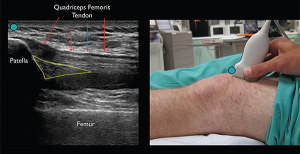

Figure 2. Identify the patella and then slide the transducer cephalad until the approach ultrasound landmarks, including the patella, femur, quadriceps femoris tendon, and fat pad, are appreciated. The effusion will appear as an anechoic (black) space underneath the fat pad. (Green circle indicates ultrasound transducer directional marker.)